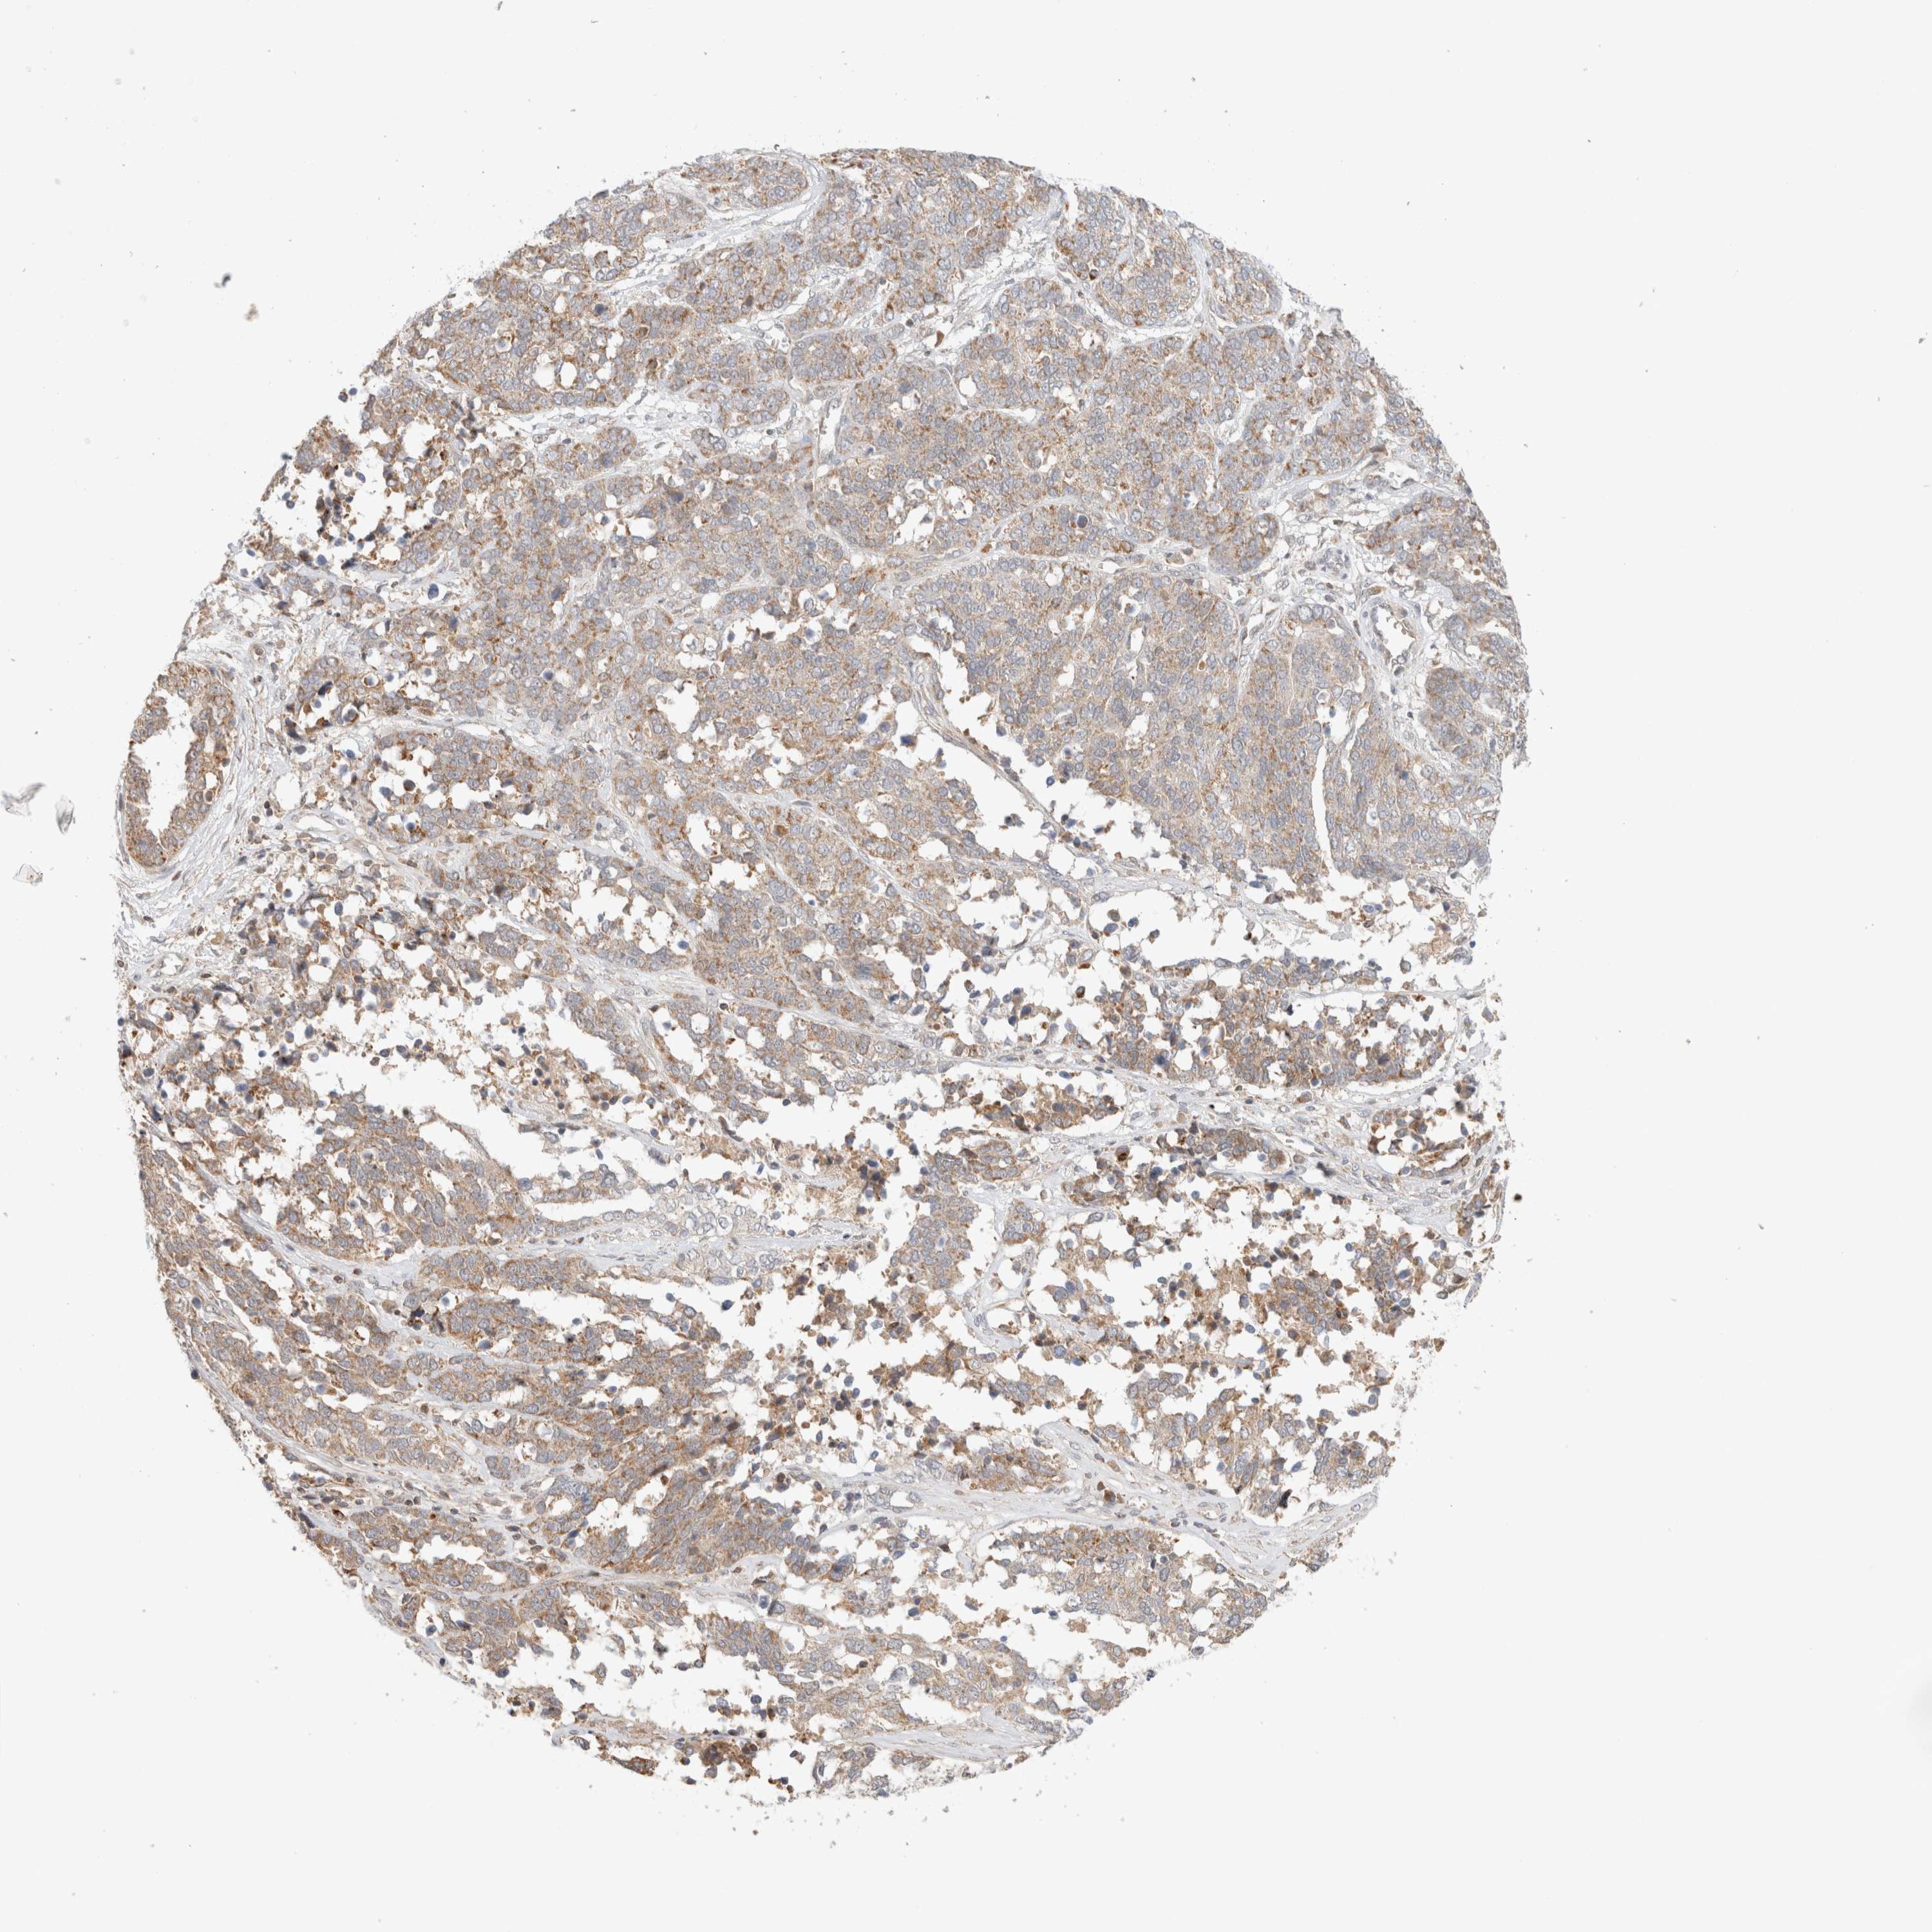

OVARIAN CANCER - Protein expressioni

A mouse-over function shows sample information and annotation data. Click on an image to view it in a full screen mode. Samples can be filtered based on level of antibody staining by selecting one or several of the following categories: high, medium, low and not detected. The assay and annotation is described here.

Note that samples used for immunohistochemistry by the Human Protein Atlas do not correspond to samples in the TCGA dataset.

Antibody stainingi

Antibody staining in the annotated cell types in the current human tissue is reported as not detected, low, medium, or high, based on conventional immunohistochemistry profiling in selected tissues. This score is based on the combination of the staining intensity and fraction of stained cells.

Each image is clickable and will lead to virtual microscopy that enables deeper exploration of all samples and also displays staining intensity scores, fraction scores and subcellular localization as well as patient and tissue information for each sample.

Antibody HPA022534

Antibody HPA023031

Antibody HPA023292

Cystadenocarcinoma, serous, NOS

Carcinoma, endometroid

Cystadenocarcinoma, mucinous, NOS

Carcinoma, NOS